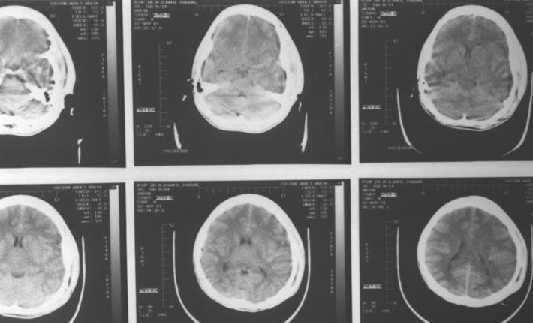

Cerebral contussions :